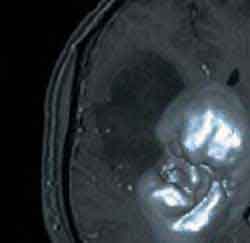

3D-модели раковых опухолей позволяют лучше понять причины рака

3D-модели также используются для изучения процессов развития раковой опухоли: ученые из Техасского университета полагают, что к раку приводит механическая деформация клеток. Для доказательства своей теории они построили 3D-модель развития раковой опухоли, в которой был продемонстрирован процесс изменения связей между клетками, в результате чего те начинали бесконтрольно делиться и образовывать опухоль.